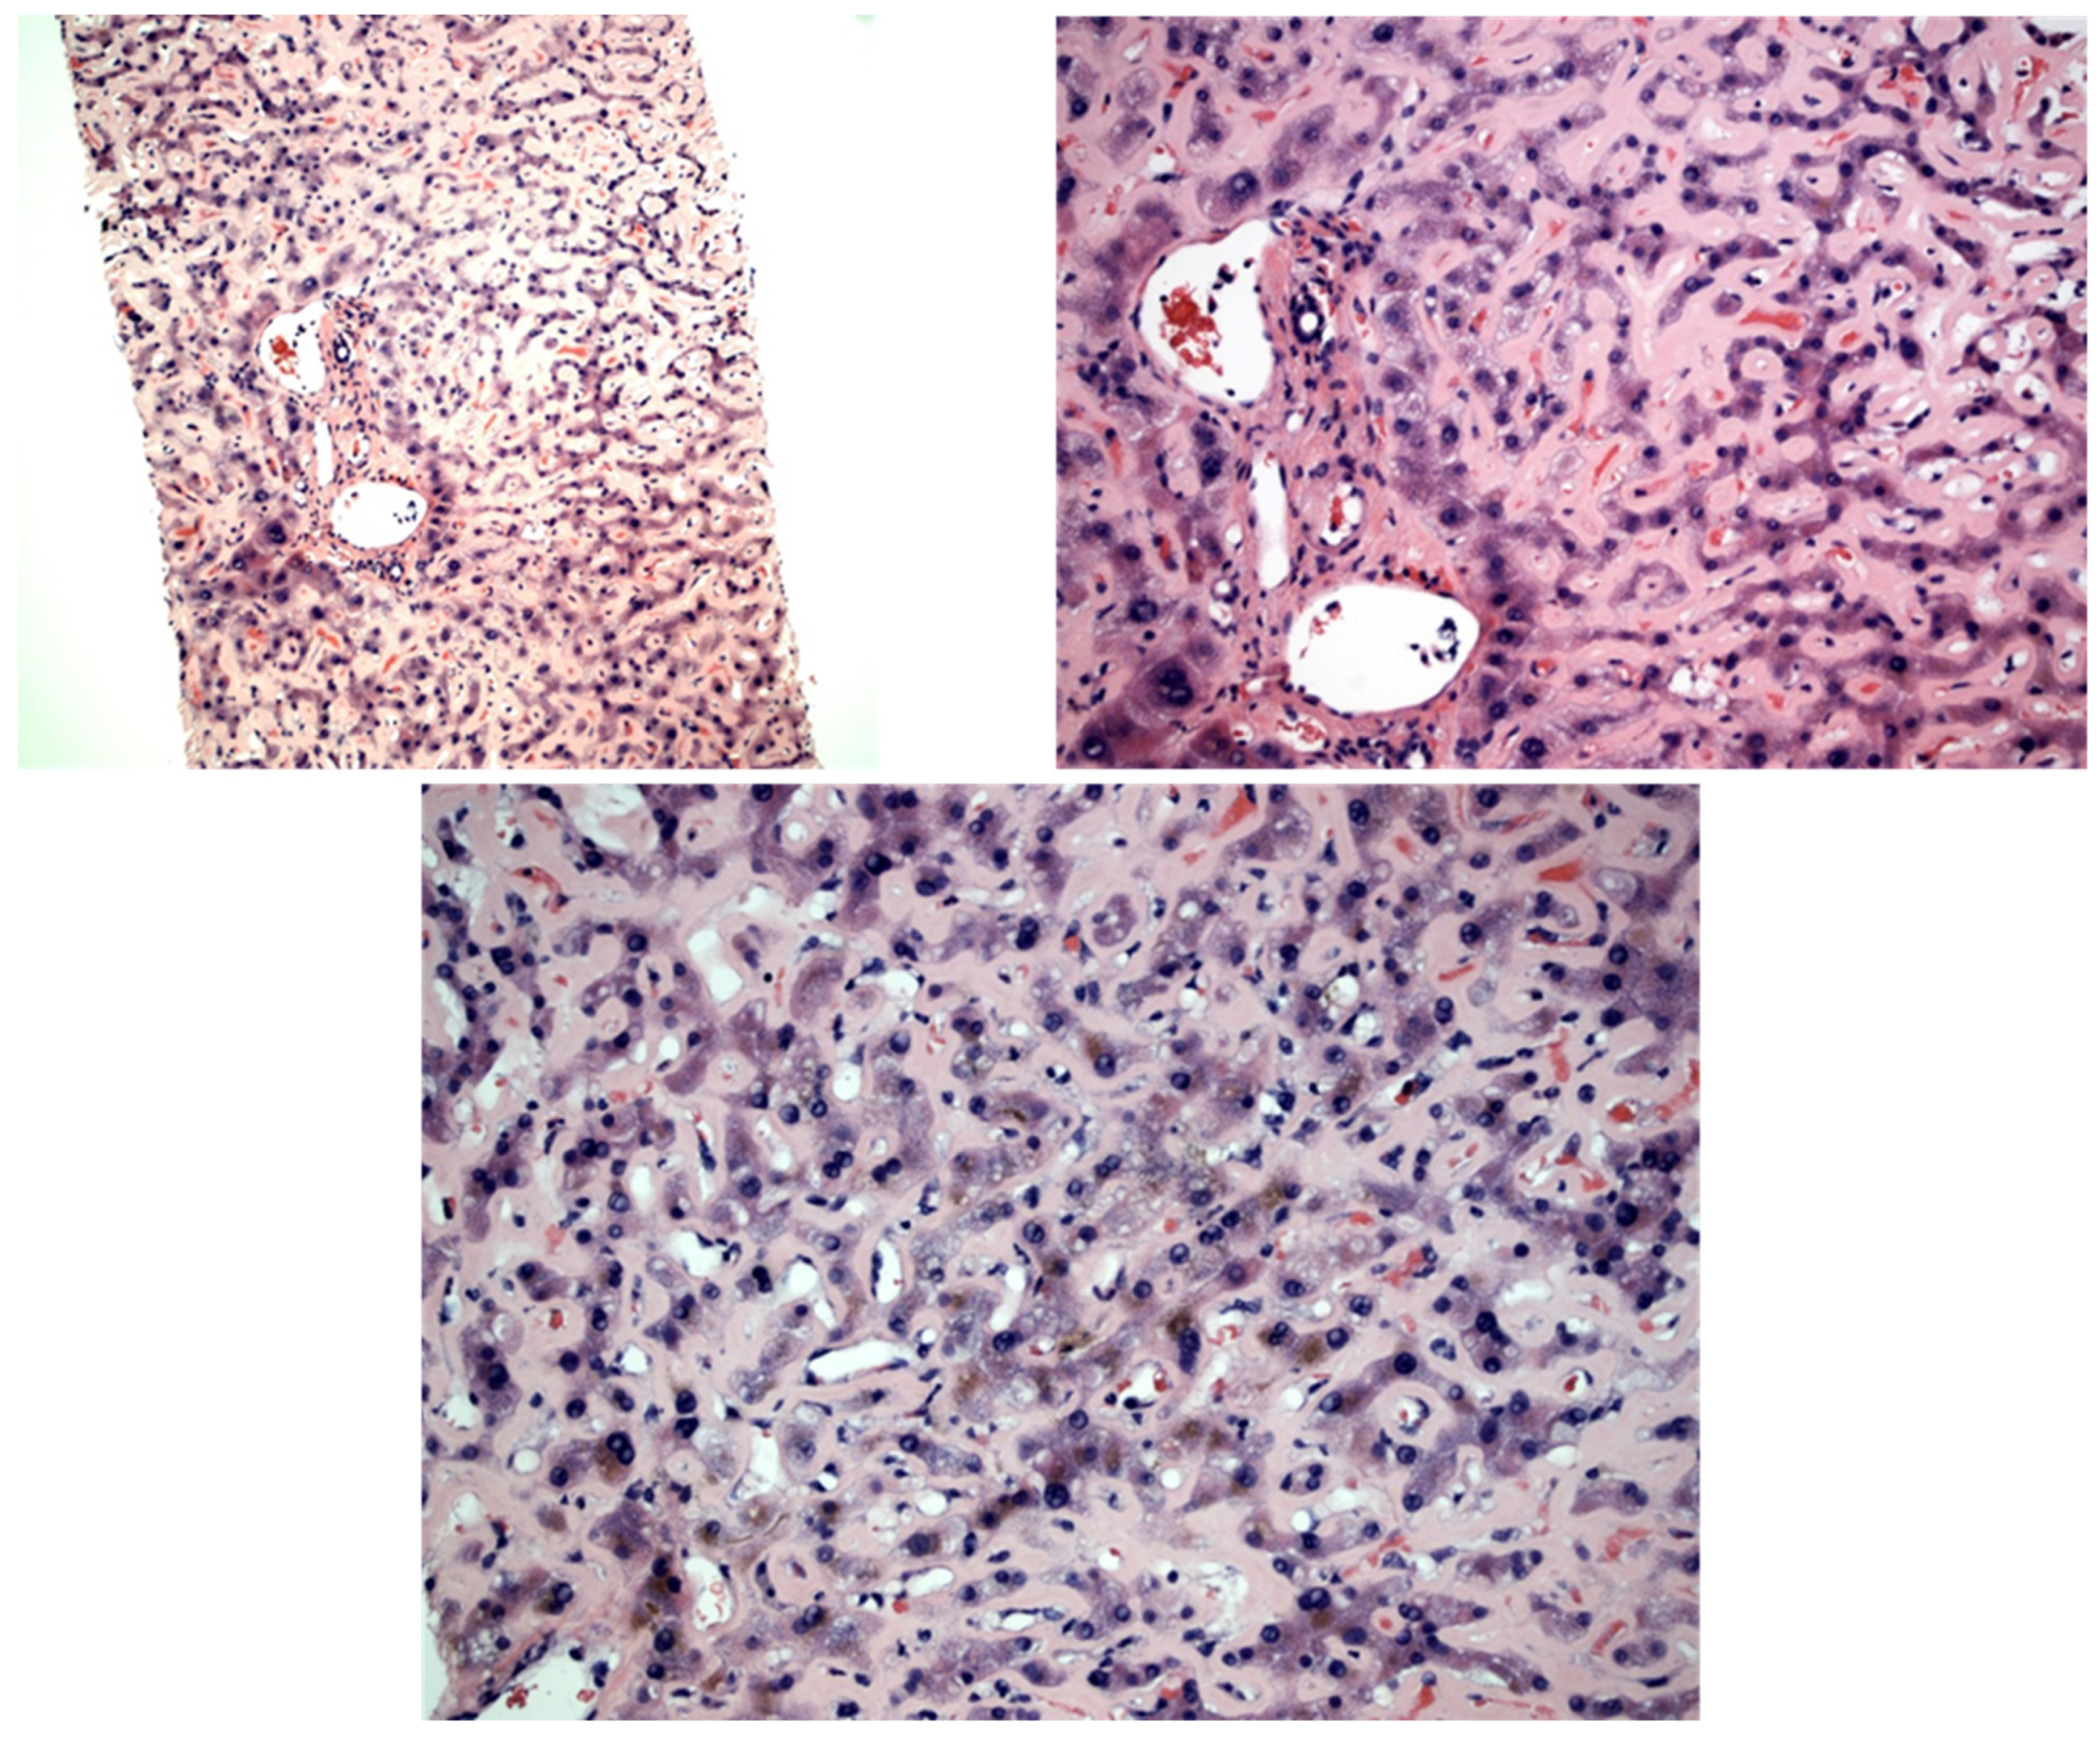

| Our study | 2022 | 83 | F | Caucasian | Generalized edema | 36.45 mg/dL | 3.2 g/dL | 289 | 95 | 1116 | 3.6 | 2.79 mg/dL | No | Yes | Yes | Supportive, CTX offered but declined | Multiorgan failure, circulatory shock; died shortly after | Monoclonal gammopathy of unknown significance | PAS positive, Congo red negative pale pink hyaline material expanding the sinusoid throughout the biopsy |